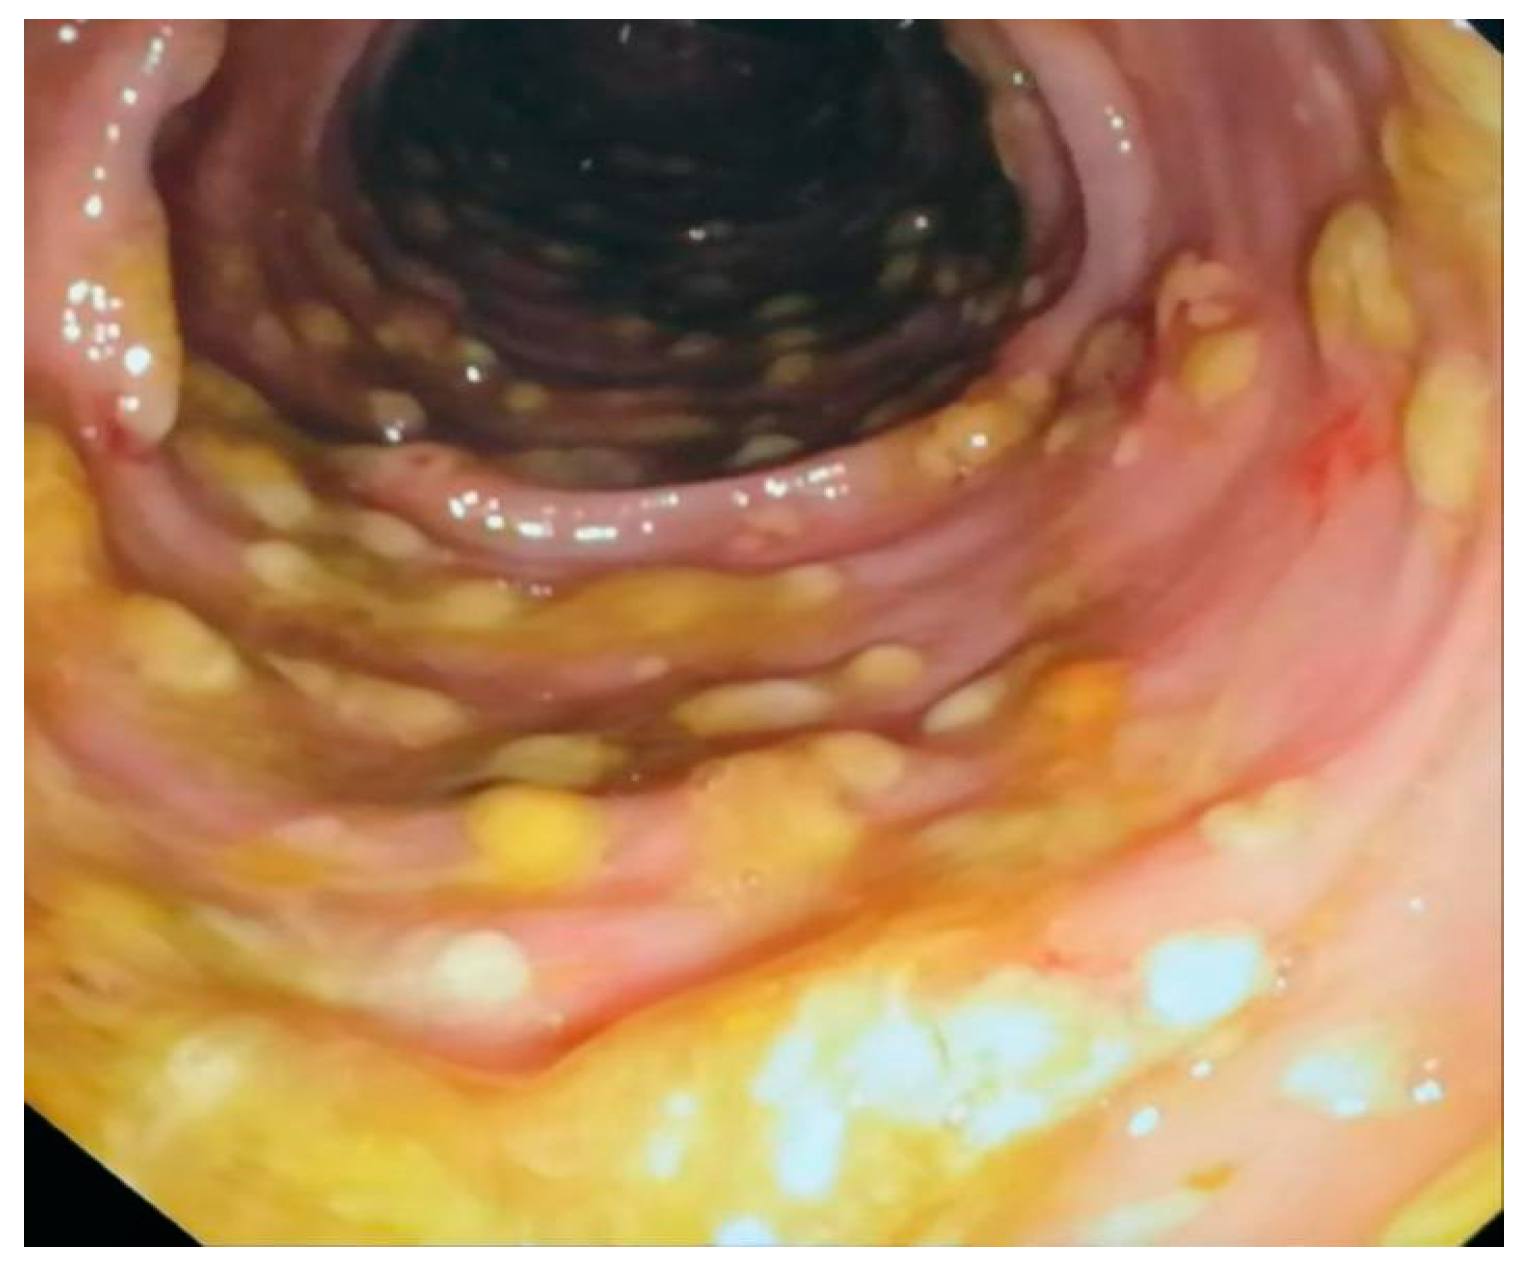

- Farooq, P.D.; Urrunaga, N.H.; Tang, D.M.; von Rosenvinge, E.C. Pseudomembranous colitis. Dis. Mon. 2015, 61, 181. [Google Scholar] [CrossRef]